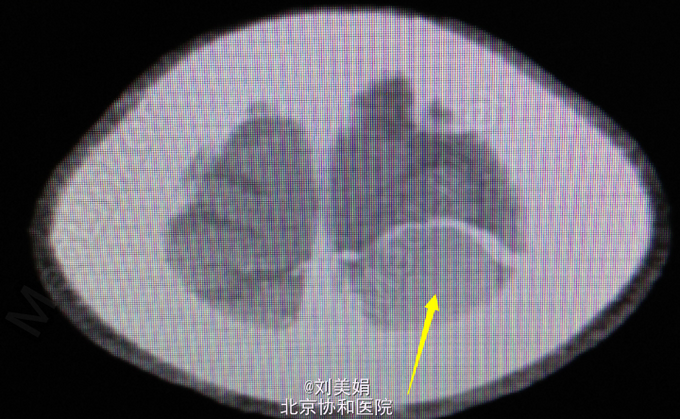

头增强CT:平扫图象显示:左侧顶部见一圆形略高密度影,边缘光整,边界清晰,大小约28.2mm×23.7mm,CT 值 68.2Hu,其内未见钙化,周围脑回受压、塌陷,脑室系统无扩大,脑沟裂未见增宽。中线结构未见明显移位。 增强图象显示:病灶明显均匀强化。CT 值为 92Hu,密度均匀,边缘清晰。右侧筛窦密度增高。